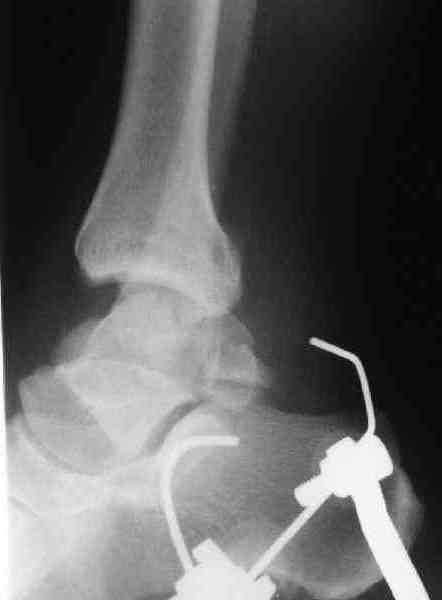

Идеально фиксацию провести в первые часы, но не всегда возможно из-за отека, поэтому временный наружный фиксатор на дистракцию поможет уменьшению отека и даст время для адекватного обследования.

При в первом типе придерживаемся закрытой репозиции, а у всех остальных в зависимости от смещения предпочитаем открытую репозицию, фиксация шурупами или пластиной. Пластина 2.4 мм более предпочтительна для удержания мелких костных осколков.

В вашем случае доступ через перелом медиальной лодыжки, обычный доступ через остеотомии лодыжки, где имеется возможность прямой репозиции тарана, после фиксации шурупами, лодыжки фиксируются обычным 2х лодыжечным методом.

Решили не связываться с остеосинтезом, а сделать сразу берцово-пяточный блок. Снимки в приложении.

По завершении удлинения, наверно, заштифтуем.

Комментарии/критика приветствуются.